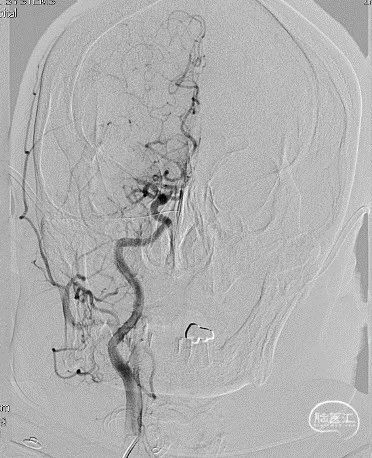

DSA造影见右侧大脑中动脉M1中段以远闭塞,ACA向MCA区域仅少量代偿。Sofia Plus在Headway21导管及Transend导丝引导下,很顺畅通过虹吸段等部位,到达M1中段。

采用ADAPT技术,血流快速复通;最右图为Sofia Plus导管前端及取出血栓。

以Transend导丝 + Headway21导管到达M1中段,Sofia PLUS顺畅到位(M1中段),ADATP技术抽吸取栓,一次成功取通,前向血流恢复至TICI3级,无栓子逃逸及原位狭窄,穿刺至开通时间20min(患者术中间断躁动不配合)。

以Sofia Plus进行抽吸取栓1次(ADAPT技术),实现血流复通(TICI 3级)